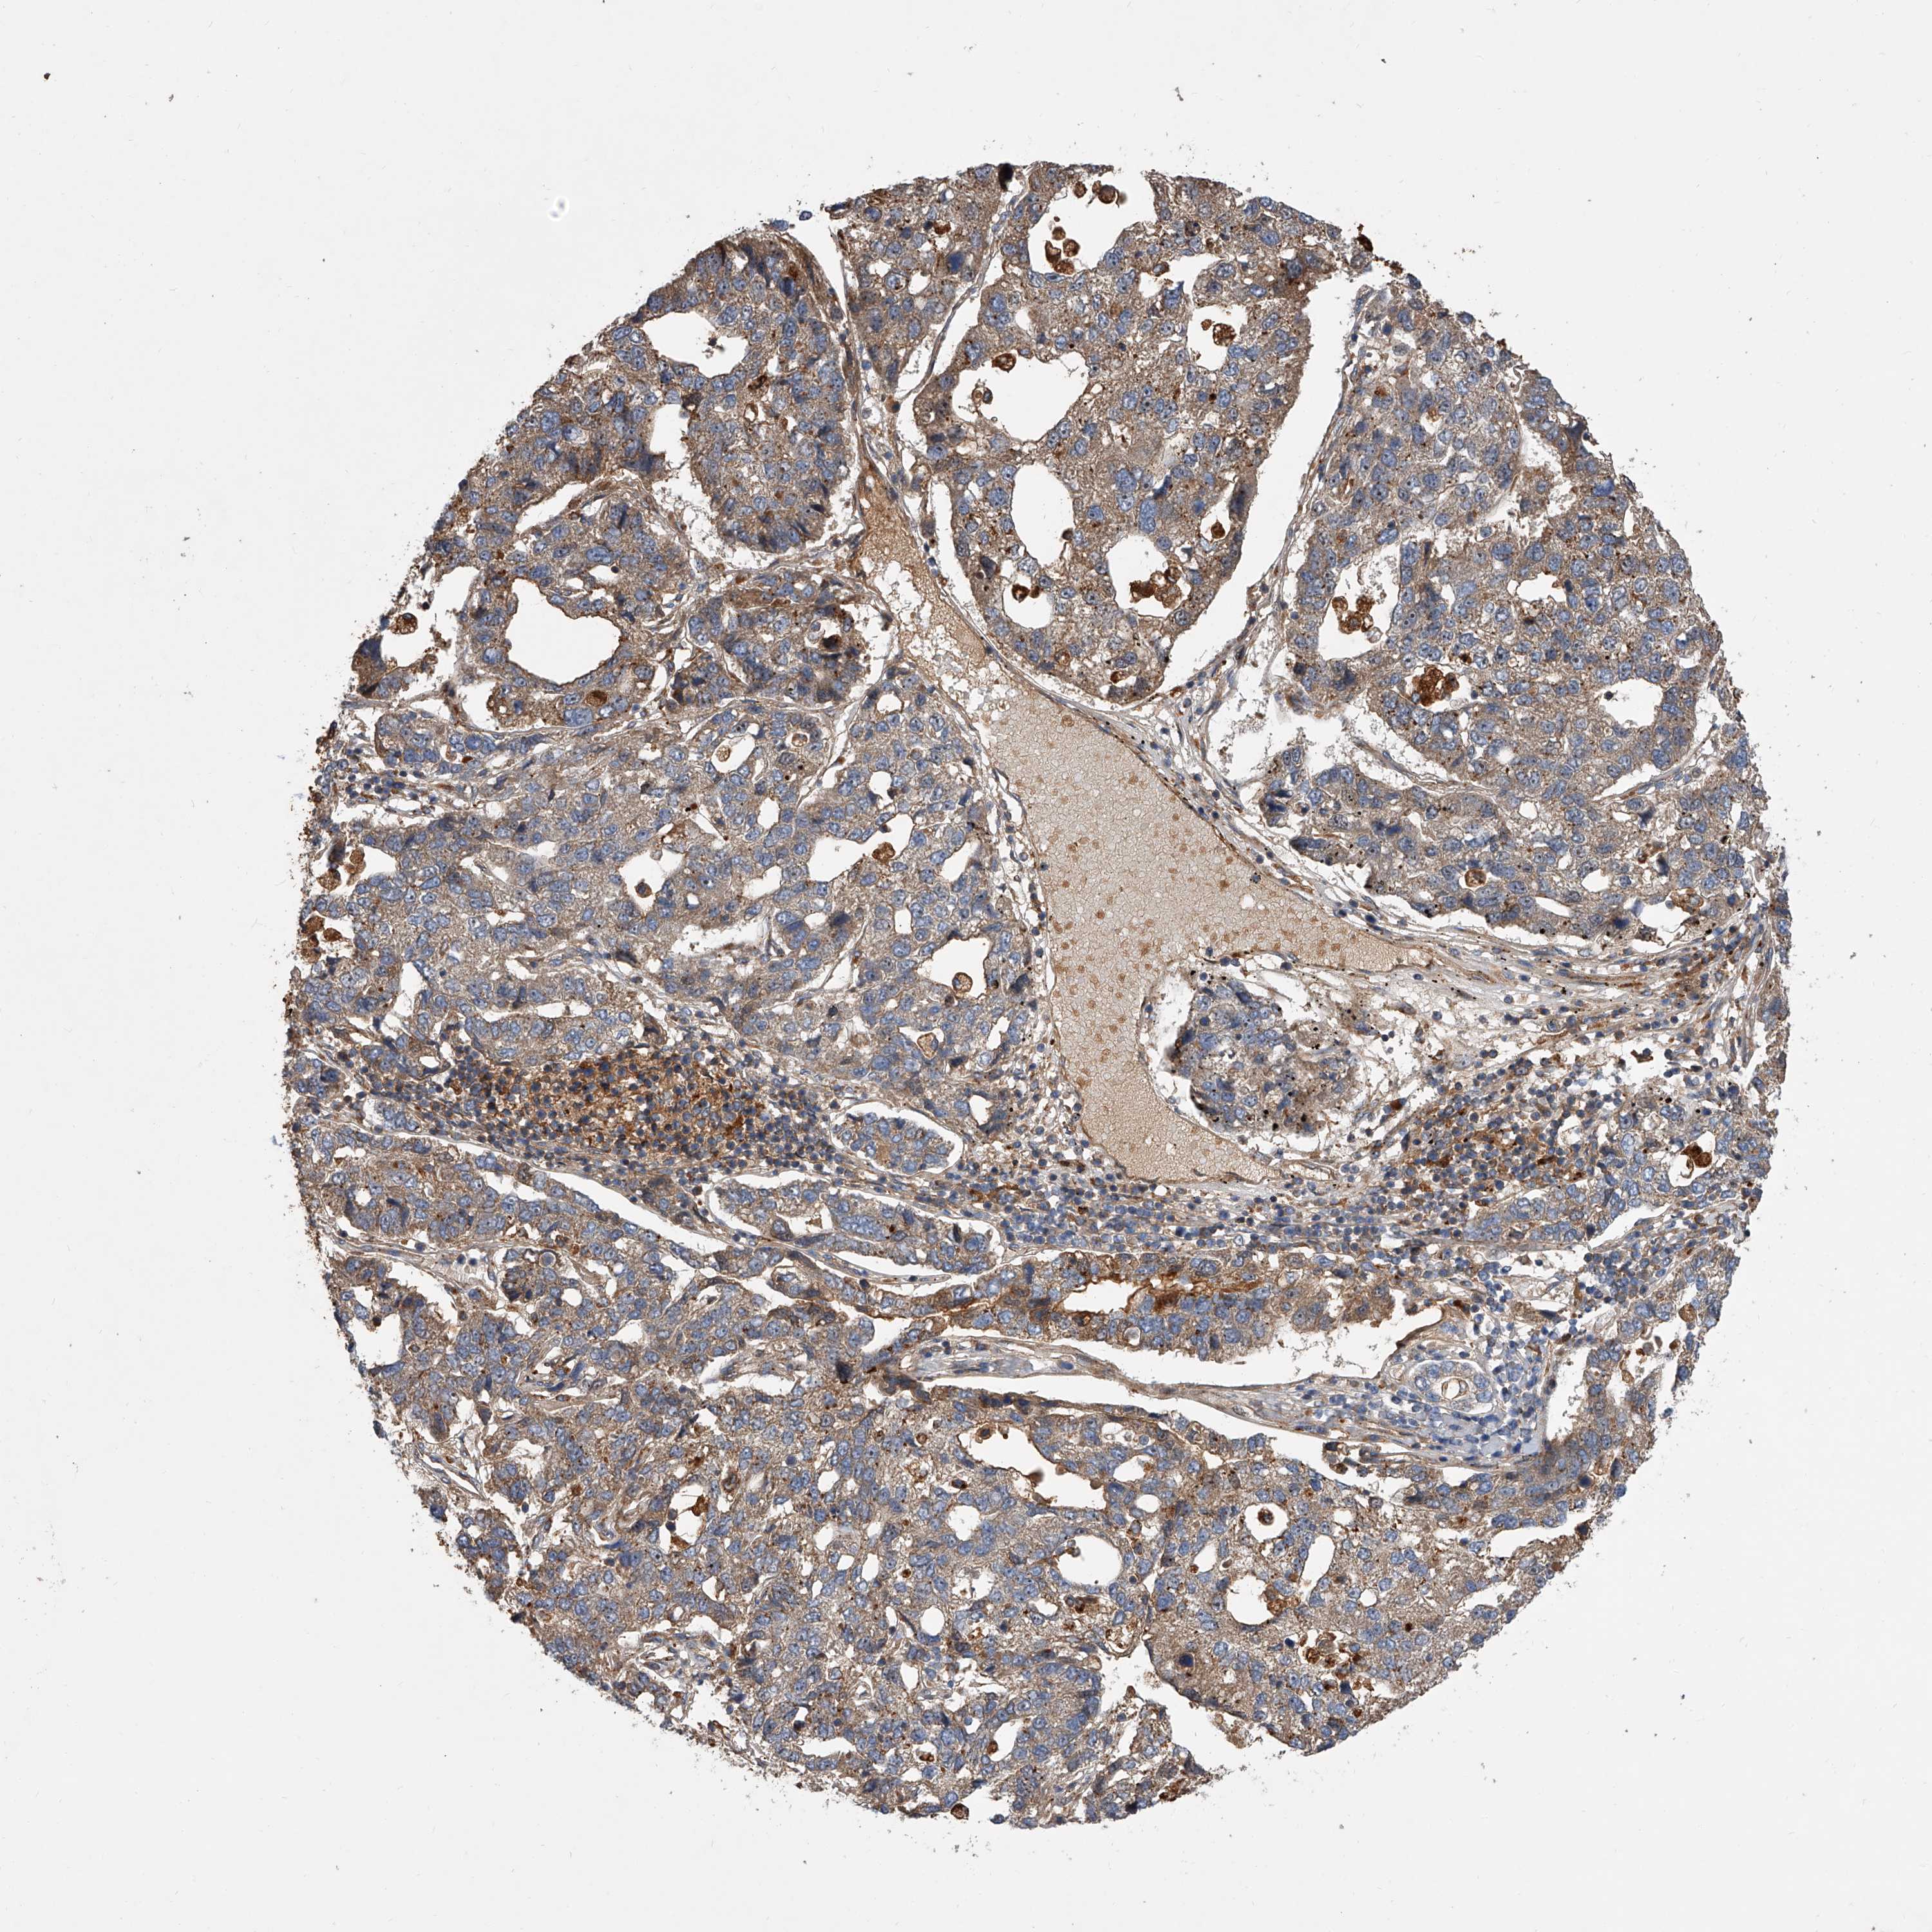

PANCREATIC CANCER - Protein expressioni

A mouse-over function shows sample information and annotation data. Click on an image to view it in a full screen mode. Samples can be filtered based on level of antibody staining by selecting one or several of the following categories: high, medium, low and not detected. The assay and annotation is described here.

Note that samples used for immunohistochemistry by the Human Protein Atlas do not correspond to samples in the TCGA dataset.

Antibody stainingi

Antibody staining in the annotated cell types in the current human tissue is reported as not detected, low, medium, or high, based on conventional immunohistochemistry profiling in selected tissues. This score is based on the combination of the staining intensity and fraction of stained cells.

Each image is clickable and will lead to virtual microscopy that enables deeper exploration of all samples and also displays staining intensity scores, fraction scores and subcellular localization as well as patient and tissue information for each sample.

Antibody HPA029286

Antibody HPA029289

Adenocarcinoma, NOS